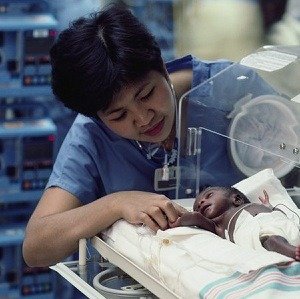

Black mothers 50% more likely to deliver premature baby vs White mothers

November 21, 2024

US Preterm Birth Rate Rises, Black Mothers Most Affected

January 31, 2024

Puerto Rican Mothers Face Alarming Birth Disparities

September 10, 2024